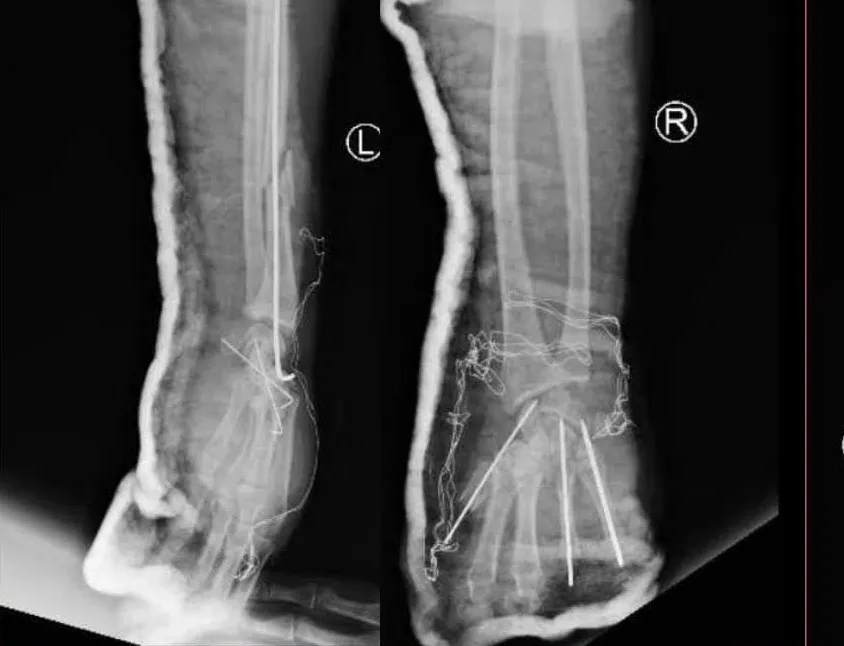

Đặc biệt, 2 bàn tay bệnh nhân bị thương rất nặng, có thể coi như nổ bung bàn tay phải, còn tay trái toác một đường dọc giữa bàn tay, lực nổ gây ép gãy cả xương quay. Các xương bàn nằm lẫn lộn, gân, cơ, thần kinh, mạch máu gần như bung hết khỏi ống cổ tay và gan tay.

Ngay lập tức, bệnh nhân được hội chẩn viện và được chuyển mổ cấp cứu. Sau 6 tiếng phẫu thuật, truyền 2 đơn vị máu, với sự tham gia của ekip gây mê, ngoại chấn thương chỉnh hình và ngoại tổng hợp, bệnh nhân được xử trí các tổn thương trong mức ổn. Hiện tại, bệnh nhân ổn định, tiếp tục được theo dõi và điều trị tích cực tại Khoa Ngoại Chấn thương chỉnh hình.